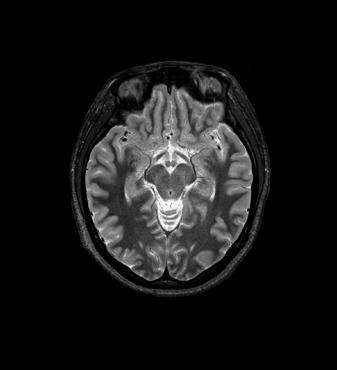

3D FLAIR with DLR. 3D FLAIR Original image. 100s, 0.5x0.5x0.6mm reconstructed

out losing time or signal. The second advantage is the reduction of image acquisition time, as we care less about the signal quality because the noise can be eleminated following the scan,” Prof. Dousset said.

DLR is more than just a new tool, it’s a major change in medical imaging history, Prof. Dousset believes. “Because the DLR will allow us to correct afterwards what couldn’t be corrected at the outset, the first application is that we no longer have to improve the signal or the spatial resolution. This is revolutionary in medical imaging history.

This is the main advantage I think: the image “denoising” technique.”

In particular DLR has an important clinical impact in anatomical regions that require a very high resolution, for example parts of the hippocampus and the claustrum.

“The DLR brings a spatial resolution that I have never seen before in neurologic imaging. I recently pointed out a brain area, for example the claustrum, that is almost invisible on standard MRI images even with very high resolution or high field devices. However, thanks

to the DLR we could highlight this kind of brain anatomy. So, indeed, there is a considerable advantage to using this technique.” Prof. Dousset said.

Prof. Tourdias worked at 7T to visualise extremely fine structures of the hippocampus while at Stanford. With DLR, he can now do this task with a 3T. “When we compared the images we realized that by pushing the 3T machine and processing with DLR that we were able to achieve a similar result to what we could achieve with 7T. I think this is the main surprise of the technology.” he said.

Original Coronal T2w image.

Coronal T2w image with DLR.

Brain Atlas SPEEDER Head/Neck, 3D FLAIR, AiCE, Res: 1 x 1 x 1.1 mm, Scan time: 4:55 min.